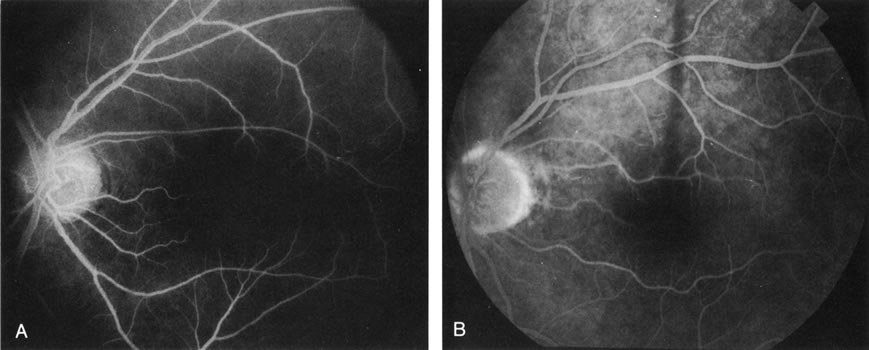

Central serous chorioretinopathy (CSC) is characterized by breakdown of the outer retinal barrier, with leakage of fluid through a defect in the retinal pigment epithelium into the subretinal space, resulting in a serous neurosensory detachment.78–205 The ophthalmologist can usually diagnose CSC based on the clinical examination and demographic information.93–95 Most patients with CSC are middle-aged men74 who often have type A personalities.75, 96–104 CSC has also been associated to the use of corticosteroids,105–118 pregnancy,119–126 increased adrenaline level and stress,127–132 hemodialysis,133,134 collagen vascular diseases,135–147 and hypertension.148–157 CSC typically presents as a large serous detachment in the posterior pole without an obvious source of the subretinal fluid.76 However, because a small CNV cannot be ruled out, FA is usually done to confirm the diagnosis. Characteristically, there is a small RPE defect, which hyperfluoresces early, and then there is slow filling of the overlying neurosensory detachment, which may have a classic “smokestack” (Fig. 21) or “ink blot” (Fig. 22) appearance.158–161 Occasionally, FA demonstrates multiple sites of leakage (Figs. 23, 24, and 25). FA sometimes fails to distinguish CSC from CNV readily because fibrinous subretinal precipitates can cause slow filling of the RPE detachment, which is suggestive of CNV (Fig. 26). Sometimes peripapillary PCV can cause a neurosensory macular detachment masquerading as CSC (Fig. 27).77

Fig. 21. Central serous chorioretinopathy. A. There is a central retinal pigment epithelium (RPE) detachment with linear RPE hyperplasia in a “hot-cross bun” configuration, indicating that the RPE detachment is chronic. B. This late fluorescein photograph illustrates leakage of fluorescein into the neurosensory detachment, with a classic “smokestack” formation.